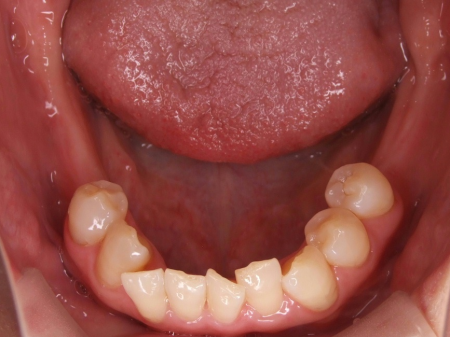

拝見したところ、歯と歯が並ぶ土台の骨「歯槽基底」の大きさの不調和により歯並びがガタガタになる「叢生(そうせい)」が全体的に生じており、また上下の前歯の重なりが深いため下の歯が見えない「過蓋咬合(かがいこうごう)」も認められました。

下の奥歯5本(右第2小臼歯/5番、左右第1大臼歯/6番、左右第2大臼歯/7番)が欠損したまま長く放置されていたことが原因で、噛み合う歯がなかった左上の奥歯(第1大臼歯)は本来の位置より下に伸びる「挺出(ていしゅつ)」が起き、左下の歯2本(第1小臼歯/4番、第2小臼歯)も内側に倒れたことで、下前歯の叢生が悪化したと考えられます。